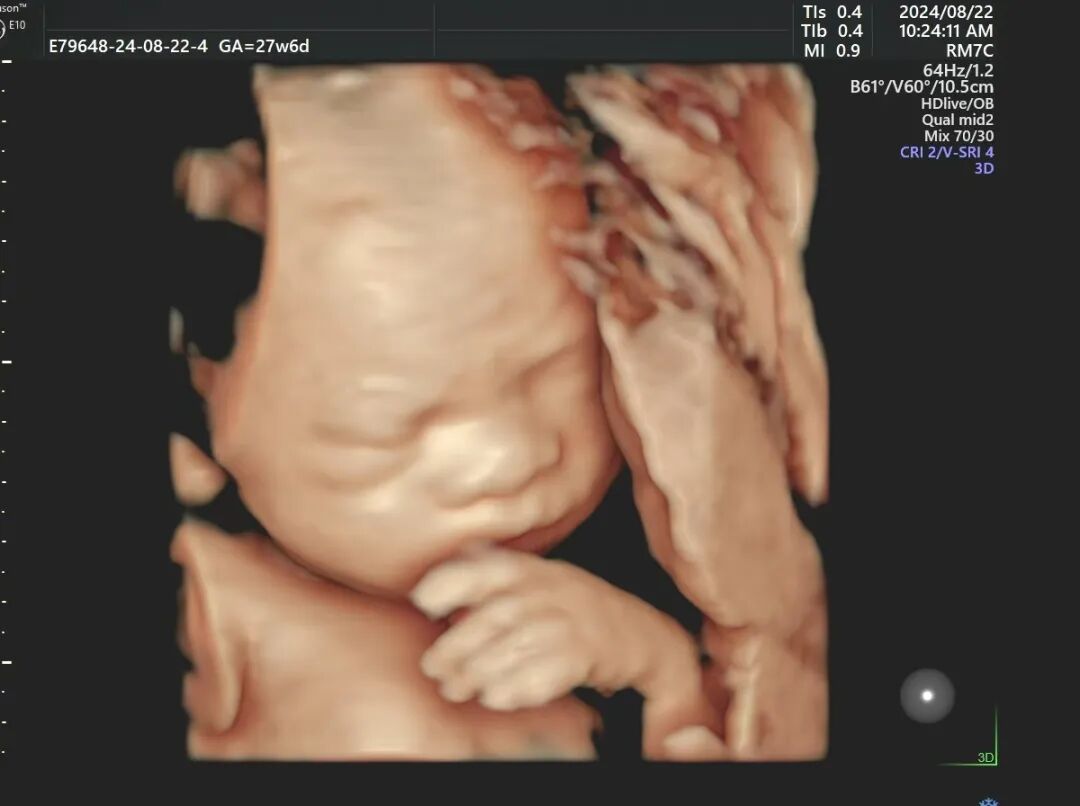

没想到小叶出去走了二十多分钟,回来后宝宝又趴着了,还是照不到。小叶又去爬楼梯,来来回回折腾了好几次,腿都麻了,做一次四维彩超真是把小叶折腾的够呛。

这次,宝宝好像听懂话了,终于把正脸转过来了,TA长得跟小叶可真像~望着墙上的图像,小叶很激动,这一刻,她感觉辛苦都是值得的。

“我们医院采用的设备是四维E10,清晰度、性能上更强,能实时捕捉宝宝的动态画面,显示出胎儿的颜色、面、各器官,发现胎儿畸形、唇裂、腭裂、骨骼发育异常等;还有胎儿的心脏、脐带、血流变化、中枢系统及脊柱等,提供更精准、更直观的图像。”医生介绍道。